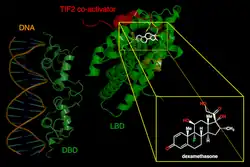

Exogenous steroid use is the most frequent cause of adrenal insufficiency, and patients who use these drugs also run the risk of experiencing an adrenal crisis.[11] Adrenal crisis can result from abrupt, and frequently unintentional, steroid withdrawal. Therefore, a thorough drug history is crucial, especially in cases of covert steroid use. The hypothalamus-pituitary-adrenal axis has been reported to be suppressed by the use of glucocorticoids in rectal,[19] paraspinal,[20] intradermal,[21] intraarticular,[22] injectable,[23] nasal,[24] inhaled,[25] or topical preparations.[26] At pharmacological dosages, medroxyprogesterone and megestrol also exhibit a notable glucocorticoid effect.[27] This risk may increase if steroids are used concurrently with ritonavir or, which inhibit the liver's CYP3A enzyme that breaks down steroids.[28][29]

It is widely acknowledged that extra mineralocorticoid treatment is not necessary at hydrocortisone dosages greater than 50 mg/day because there is adequate action within the mineralocorticoid receptor.[8] In those who have primary adrenal insufficiency, fludrocortisone needs to be started with subsequent dose tapering; for most patients, a daily dose of 50–200 mg is adequate.[52] According to current treatment guidelines of primary adrenal insufficiency, the doses of prednisolone and dexamethasone are recommended based on their glucocorticoid potency in relation to hydrocortisone.[50]